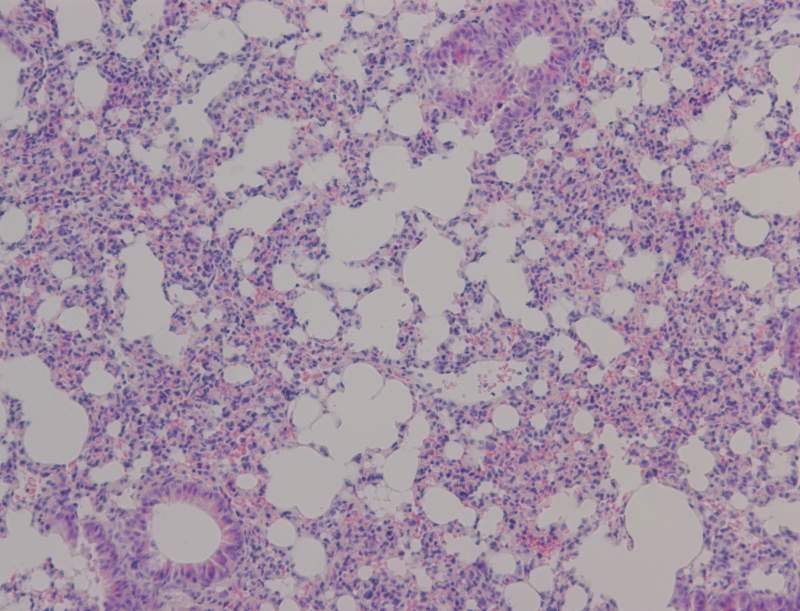

小鼠肺病理切片观察